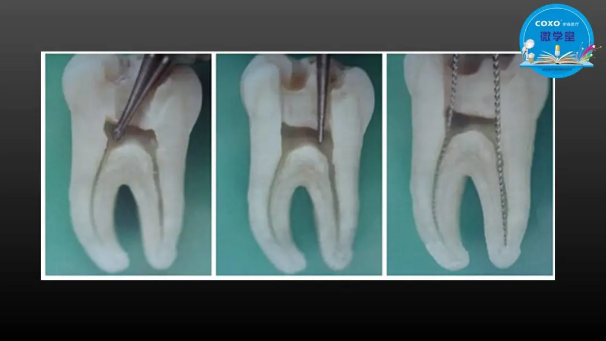

主任醫(yī)師,牙體牙髓副主任, 廣東省口腔醫(yī)院牙體牙髓科 主任醫(yī)師。2003年碩士研究生畢業(yè),研究方向為牙體牙髓病學,擅長于牙體牙髓病的診斷、齲齒、牙髓炎、根尖周病的治療以及前牙美容修復。